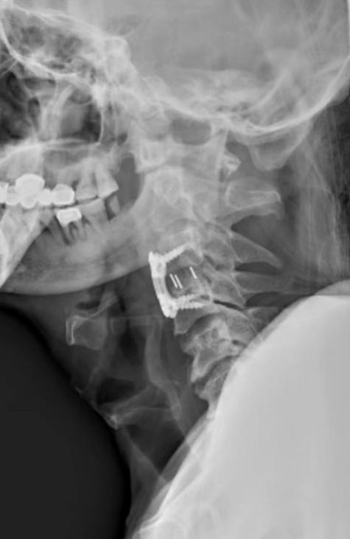

术后影像:患者颈椎神经压迫情况得到及时缓解

抢救生命刻不容缓,由陈钢指导,龚飞鹏副主任医师、龙智生副主任医师、温家宾主治医师组成的治疗小组为患者急诊实施了颈椎前路手术。手术将患者颈椎压迫脊髓的巨大椎间盘彻底清除,把脊髓彻底“解放”出来了,而手术时间仅一个多小时,切口只有4cm长。术后第2天,奇迹出现了!患者的下肢开始能够自己活动了,肌力由手术前的0级变成了手术后的2级,呼吸也趋于平稳,患者和家属喜出望外,虽然离最后的康复还要花费很多的时间和精力,但奇迹的发生已经让患者对生活重燃信心和希望。一周后,患者双上肢肌力也恢复到2级,可以活动双手双腿,患者和家属都非常高兴和激动。为进一步专业化治疗,涂先生现已转入康复医院,肌肉力量仍在持续恢复中。